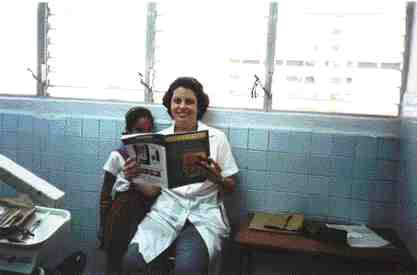

General Dentistry: A New Nonsurgical Treatment for Periodontal Patients Who Refuse Surgery

Most general practitioners have many patients with moderate to advanced periodontal disease who refuse to have surgical treatment. The author, a periodontist, his brother a general practitioner and their father a periodontist developed, tested and used a nonsurgical approach on such patients that was very effective. About two years ago the author, at the urging … Read more